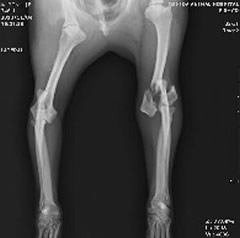

粉砕骨折

左肘の骨が5つの骨に割れており、通常のプレート固定では不可能な状態です。